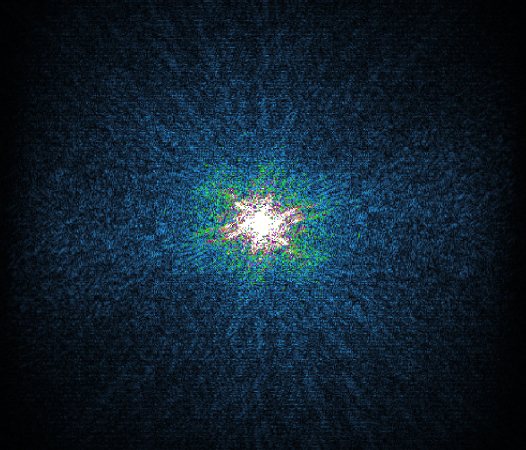

In the example below, only one fifth of the required MR radiofrequency signals is recorded. This results in a five times faster acquisition, with a subsampled k-space (top left) and inherent image artifacts after standard reconstruction (top right).

Philips Compressed SENSE

The Compressed SENSE reconstruction then uses iterative, knowledge-based algorithms to fill in the empty lines in k-space (bottom left). This removes the artifacts while keeping the final image fully consistent with the acquired data (bottom right). *Compared to Philips MR exams without Compressed SENSE